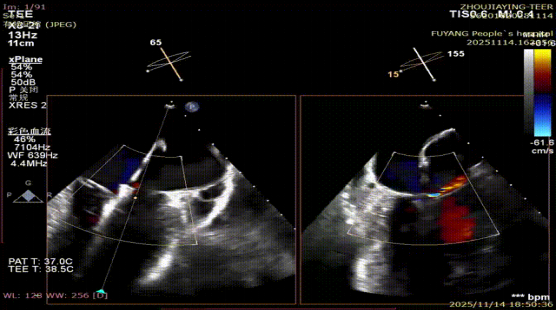

手术当日,在全身麻醉及TEE全程导航下,陈玺全副主任团队凭借丰富的临床经验与精湛操作技巧,顺利完成房间隔穿刺、瓣叶精准定位等关键步骤。针对患者二尖瓣A2/P2 区域反流靶点,团队精准夹合瓣叶,经X-plane技术与三维超声反复确认夹持质量后,成功释放一枚MitraClip XTR夹子。术后即时评估显示,患者二尖瓣反流由术前3 +重度降至轻度,平均跨瓣压仅3mmHg,手术达到预期效果,全程无并发症发生。

术前MR反流